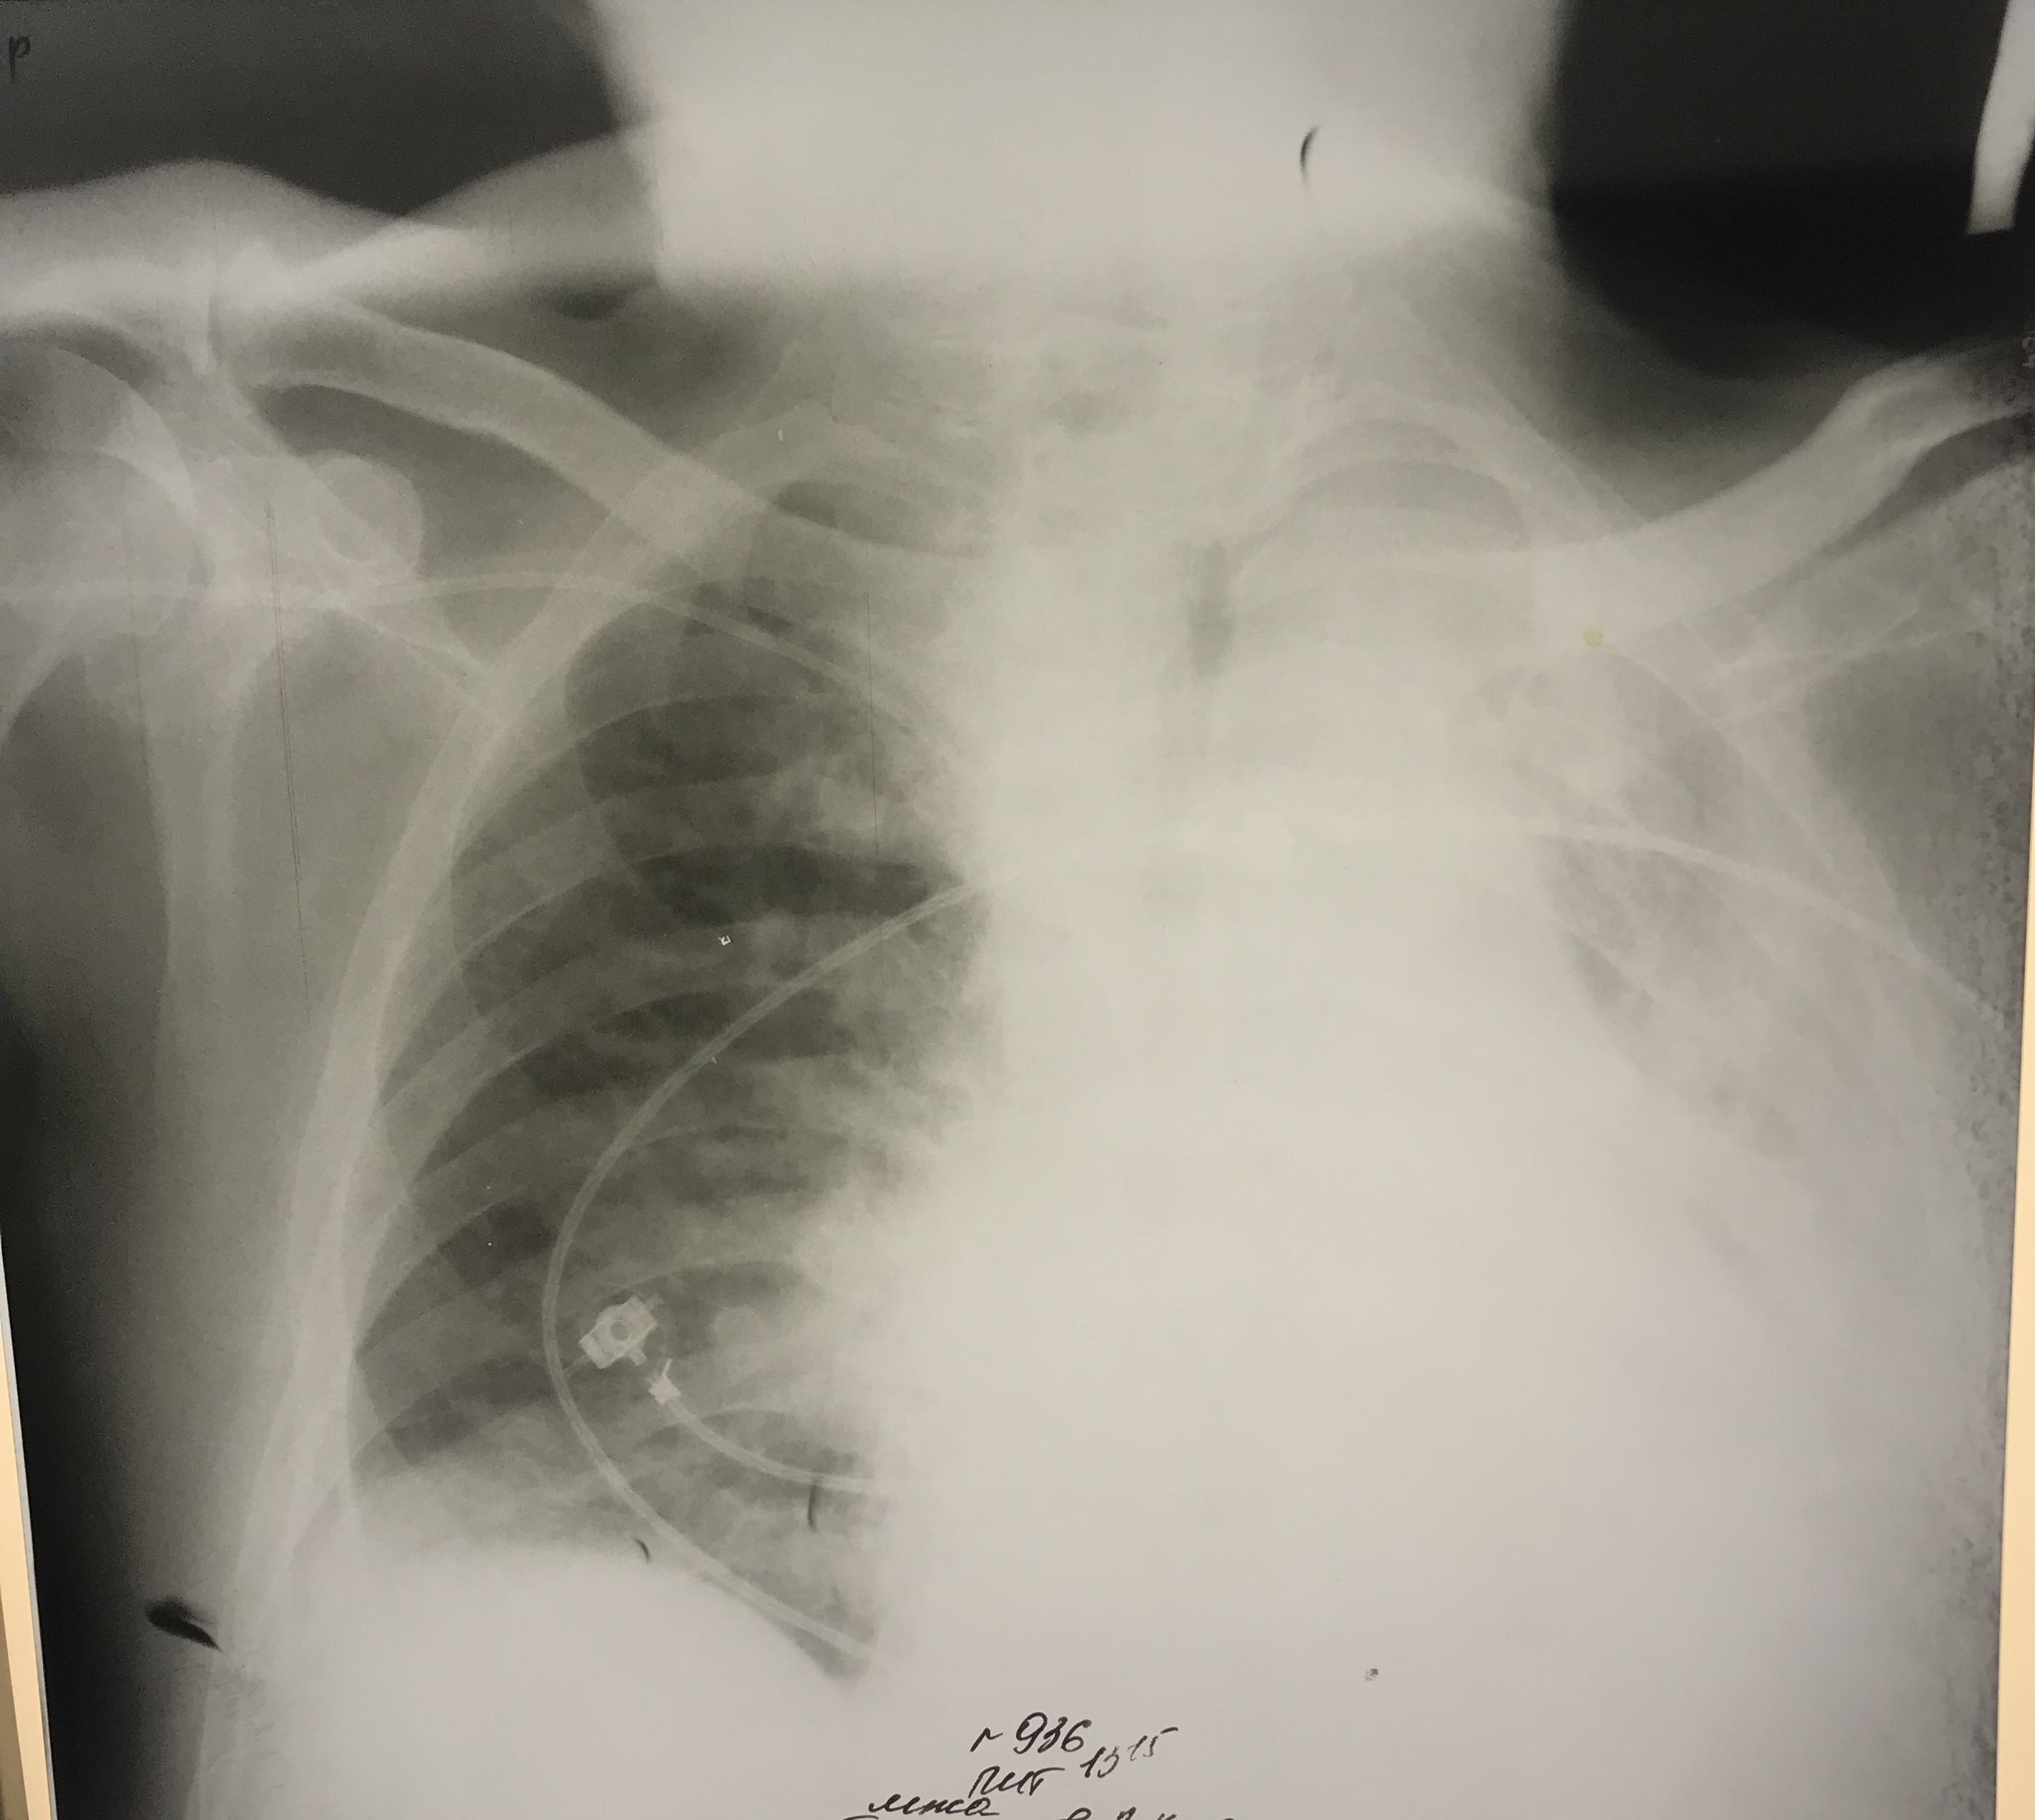

Ателектаз слева. Гнойный эндобронхит с закупоркой бронхов гноем.

Ателектаз слева. Центральный рак.

Ателектаз справа. Центральный рак.

Ателектаз у больного с инсультом